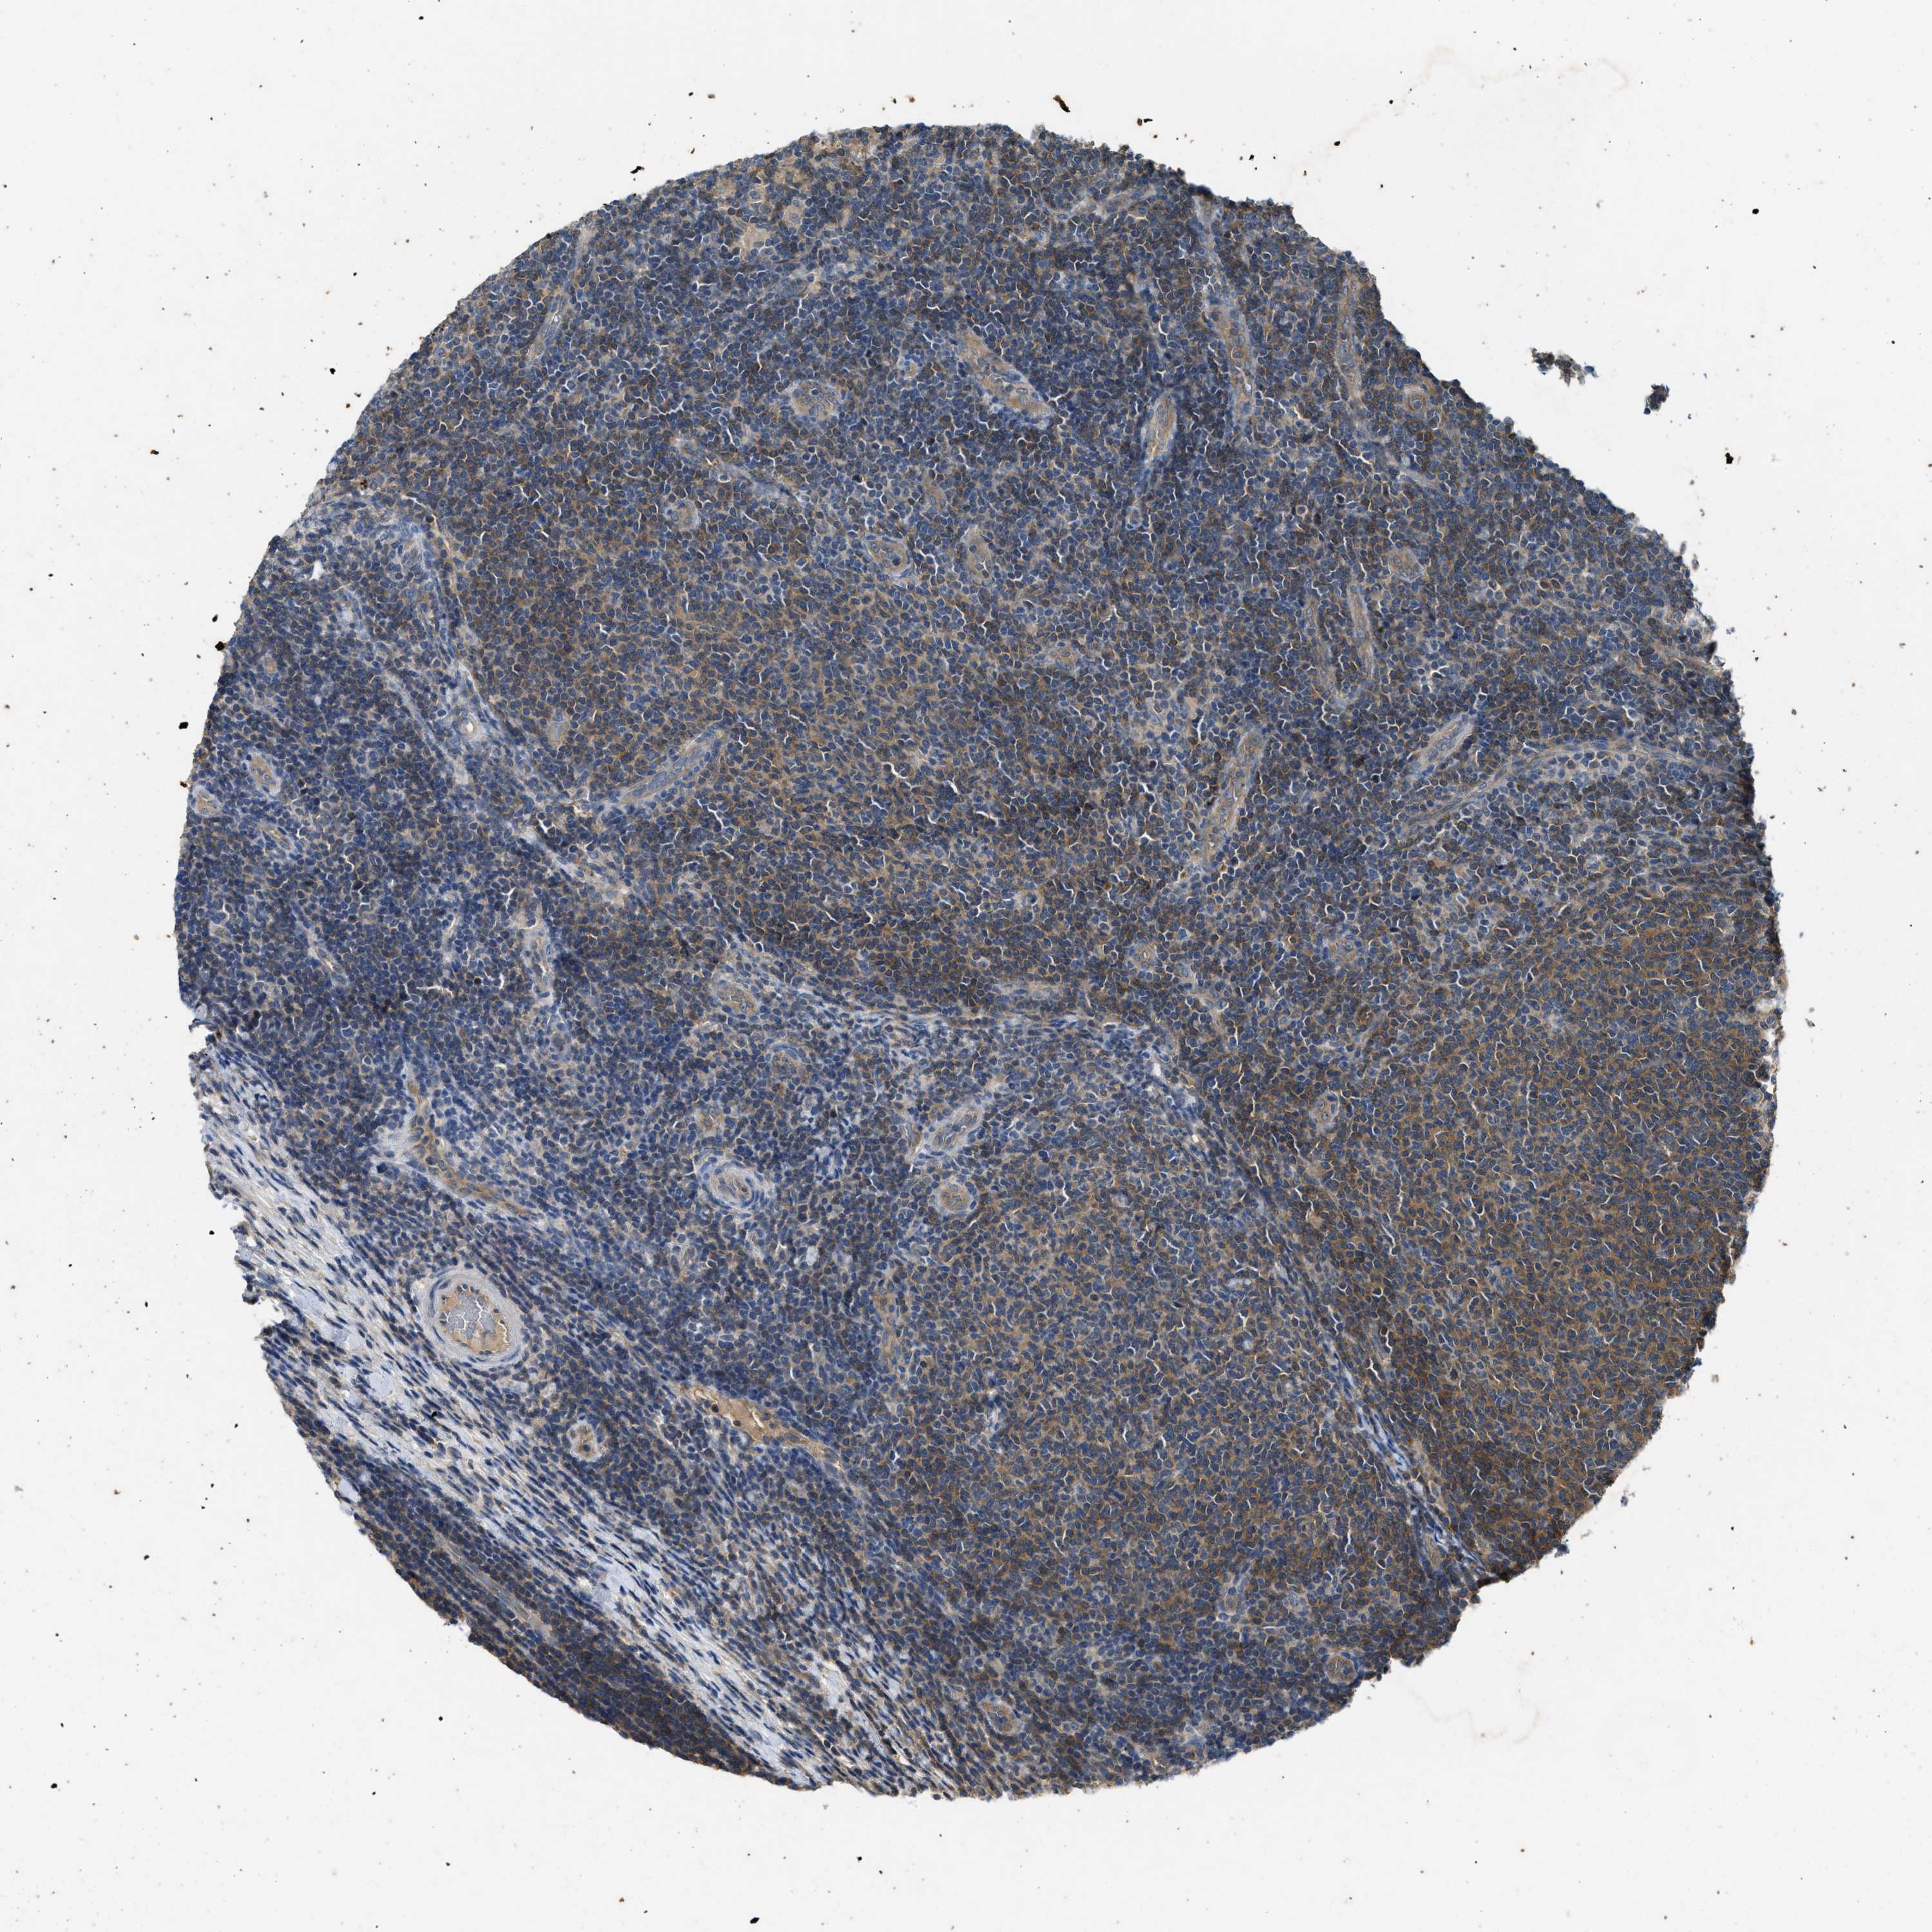

CANCER LYMPHOMA Show tissue menu

LYMPHOMA - Protein expressioni

A mouse-over function shows sample information and annotation data. Click on an image to view it in a full screen mode. Samples can be filtered based on level of antibody staining by selecting one or several of the following categories: high, medium, low and not detected. The assay and annotation is described here.

Antibody stainingi

Antibody staining in the annotated cell types in the current human tissue is reported as not detected, low, medium, or high, based on conventional immunohistochemistry profiling in selected tissues. This score is based on the combination of the staining intensity and fraction of stained cells.

Each image is clickable and will lead to virtual microscopy that enables deeper exploration of all samples and also displays staining intensity scores, fraction scores and subcellular localization as well as patient and tissue information for each sample.

Antibody HPA012778

Antibody CAB018581

Staining

High

Medium

Low

Not detected

Intensity

Strong

Moderate

Weak

Negative

Quantity

>75%

75%-25%

<25%

None

Location

Nuclear

Cytoplasmic/membranous

Cytoplasmic/membranous,nuclear

Hodgkin's disease, NOS

Malignant lymphoma, non-Hodgkin's type, High grade

Malignant lymphoma, non-Hodgkin's type, Low grade